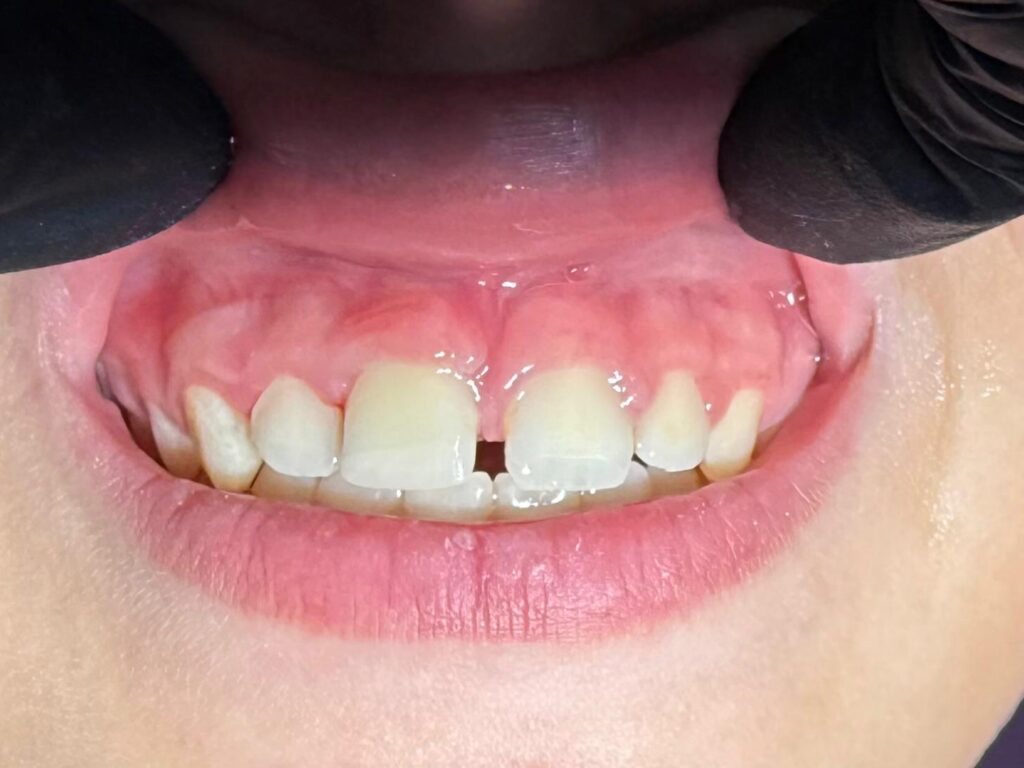

Paraqitja e pacientit dhe vlerësimi fillestar Pacientja, një vajzë 11-vjeçare, u paraqit në urgjencë së bashku me prindërit, të shqetësuar pas një rrëzimi ku kishte goditur me fytyrë dyshemenë. Trauma kishte ndodhur vetëm pak minuta para mbërritjes në klinikë, çka përbënte një avantazh të jashtëzakonshëm për prognozën e dhëmbit të dëmtuar.

Gjatë ekzaminimit klinik u vërejtën menjëherë shenjat e traumës, të shoqëruara me dhimbje, gjakderdhje dhe një boshllëk të dukshëm në regjionin e dhëmbit të sipërm qendror.

Përmes një ekzaminimi të detajuar, u evidentuan tre dëmtimet kryesore:

• Avulsion i plotë i dhëmbit 11, një dëmtim ku dhëmbi del tërësisht nga alveola, duke e bërë kohën faktor kritik.

• Frakturë e margjinales incizale rreth 2 mm, një dëmtim i lehtë i kurorës, i cili ndikon estetikën por është i menaxhueshëm.

• Trauma e alveolës në anën vestibulare, me dëmtim të indeve mbështetëse, por pa shkëputje të plotë të kockës – një element i rëndësishëm që e bënte reimplantimin të mundur dhe me shanse të mira suksesi.